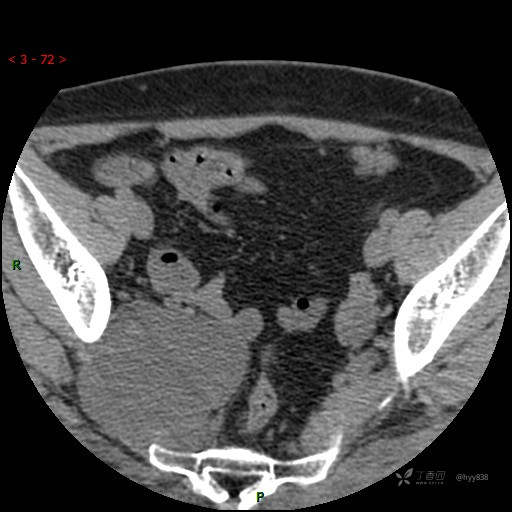

骶髂关节CT平扫